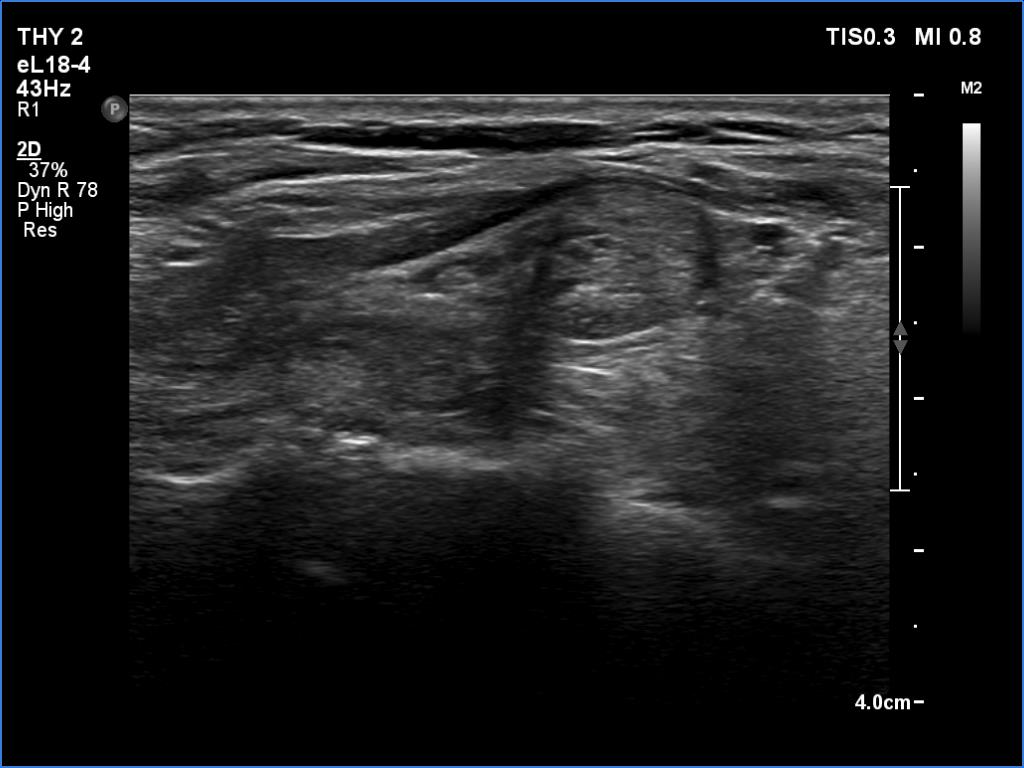

Ultrasonography. Both lobes had discrete lesions. The volume of the lobes were approximately one-tenth and one-third of a normal lobe, right and left lobe, respectively. The possibility of a true nodule should be considered in the event of the lesions in the left lobe.